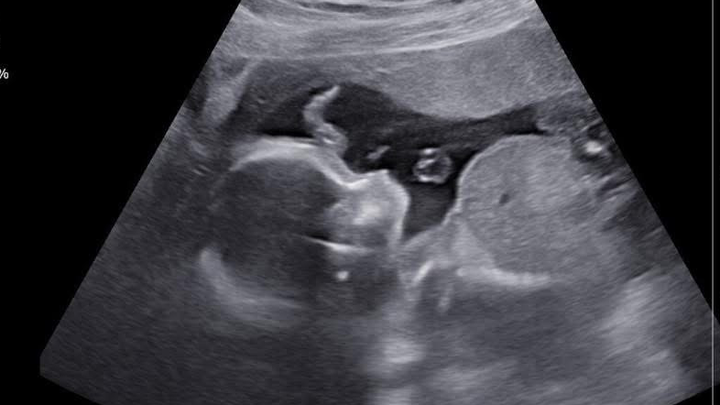

My name is Tyra and I am creating this gofund me for my sister and brother in law. Trista (my sister) has been off of work since September due to complications and sickness with her pregnancy. She was admitted to Good Sam’s with severely high blood pressure after speaking to her doctor she got transferred to St. Mary’s hospital in St. Louis Missouri. After multiple test, it has came back that she has severe preeclampsia. Trista is only 23 weeks pregnant as of 10/10. She will stay in St.Marys until she delivers her sweet baby boy. Doctors have talked as if she won’t go full term. They told her the farthest the she will go is 34 weeks and by 34 weeks they will deliver the baby if she makes it that far. Anything will help as her fiancé and family travels to her. Whether it’s for food, gas, hotel stays, anything would truly help! Please keep my sister, my nephew and brother in law in your prayers!